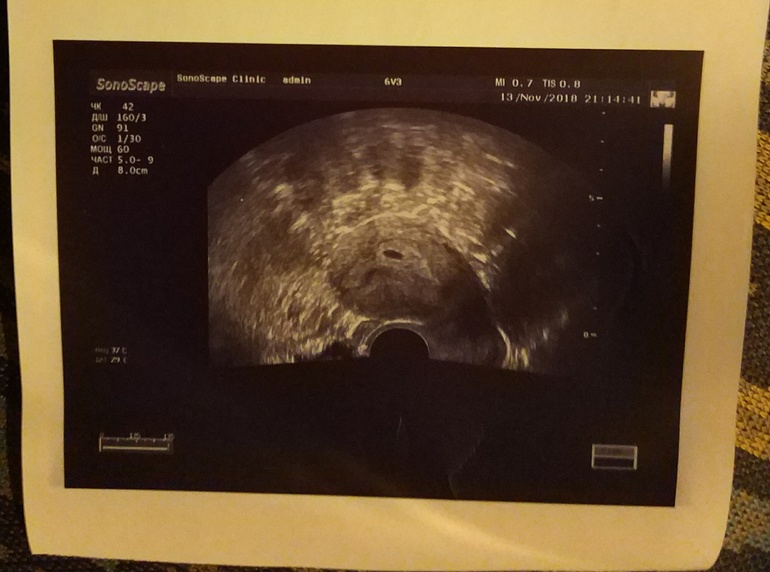

Первое фото😃

Увидела нашу крошечку, начало 6-ой акушерской/4-ой эмбриональной недели:

Из того что запомнила из комментариев врача: плодное яйцо 6 мм, жёлтое тело 15 мм (вроде).

А на следующем УЗИ, через неделю, сказали уже должно быть сердцебиение ❤️